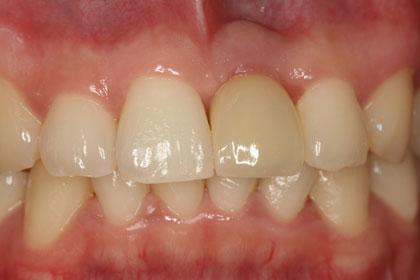

ภาพฟันถาวร

ส่วนความสวยงามโดยเฉพาะบริเวณฟันหน้าที่เกิดอุบัติเหตุ หรือต้องถูกถอนไปจากสาเหตุต่างๆ ทันตแพทย์สามารถใส่รากฟันเทียมทดแทนได้ทันที พร้อมทั้งทำฟันครอบชั่วคราวไว้ประมาณ 6 – 8 อาทิตย์ ก็จะทำการใส่ฟันถาวรได้

ปัจจุบัน ความสวยงามในฟันหน้าทันตแพทย์สามารถกำหนดได้ใกล้เคียงกับฟันธรรมชาติมากขึ้น และสำหรับผู้สูงอายุ หรือ ผู้ที่สูญเสียฟันธรรมชาติทั้งปากไป การใส่รากฟันเทียมมีส่วนเข้ามาช่วยทำให้เคี้ยวอาหารได้ดีขึ้น โดยในขากรรไกรล่างทันตแพทย์จะใส่รากฟันเทียมประมาณ 4 ราก และใส่รวมกับฟันปลอมชนิดถอดได้ทำให้ประสิทธิภาพในการใช้งานดีขึ้นทันที และสามารถใช้บดเคี้ยวอาหารได้เลย